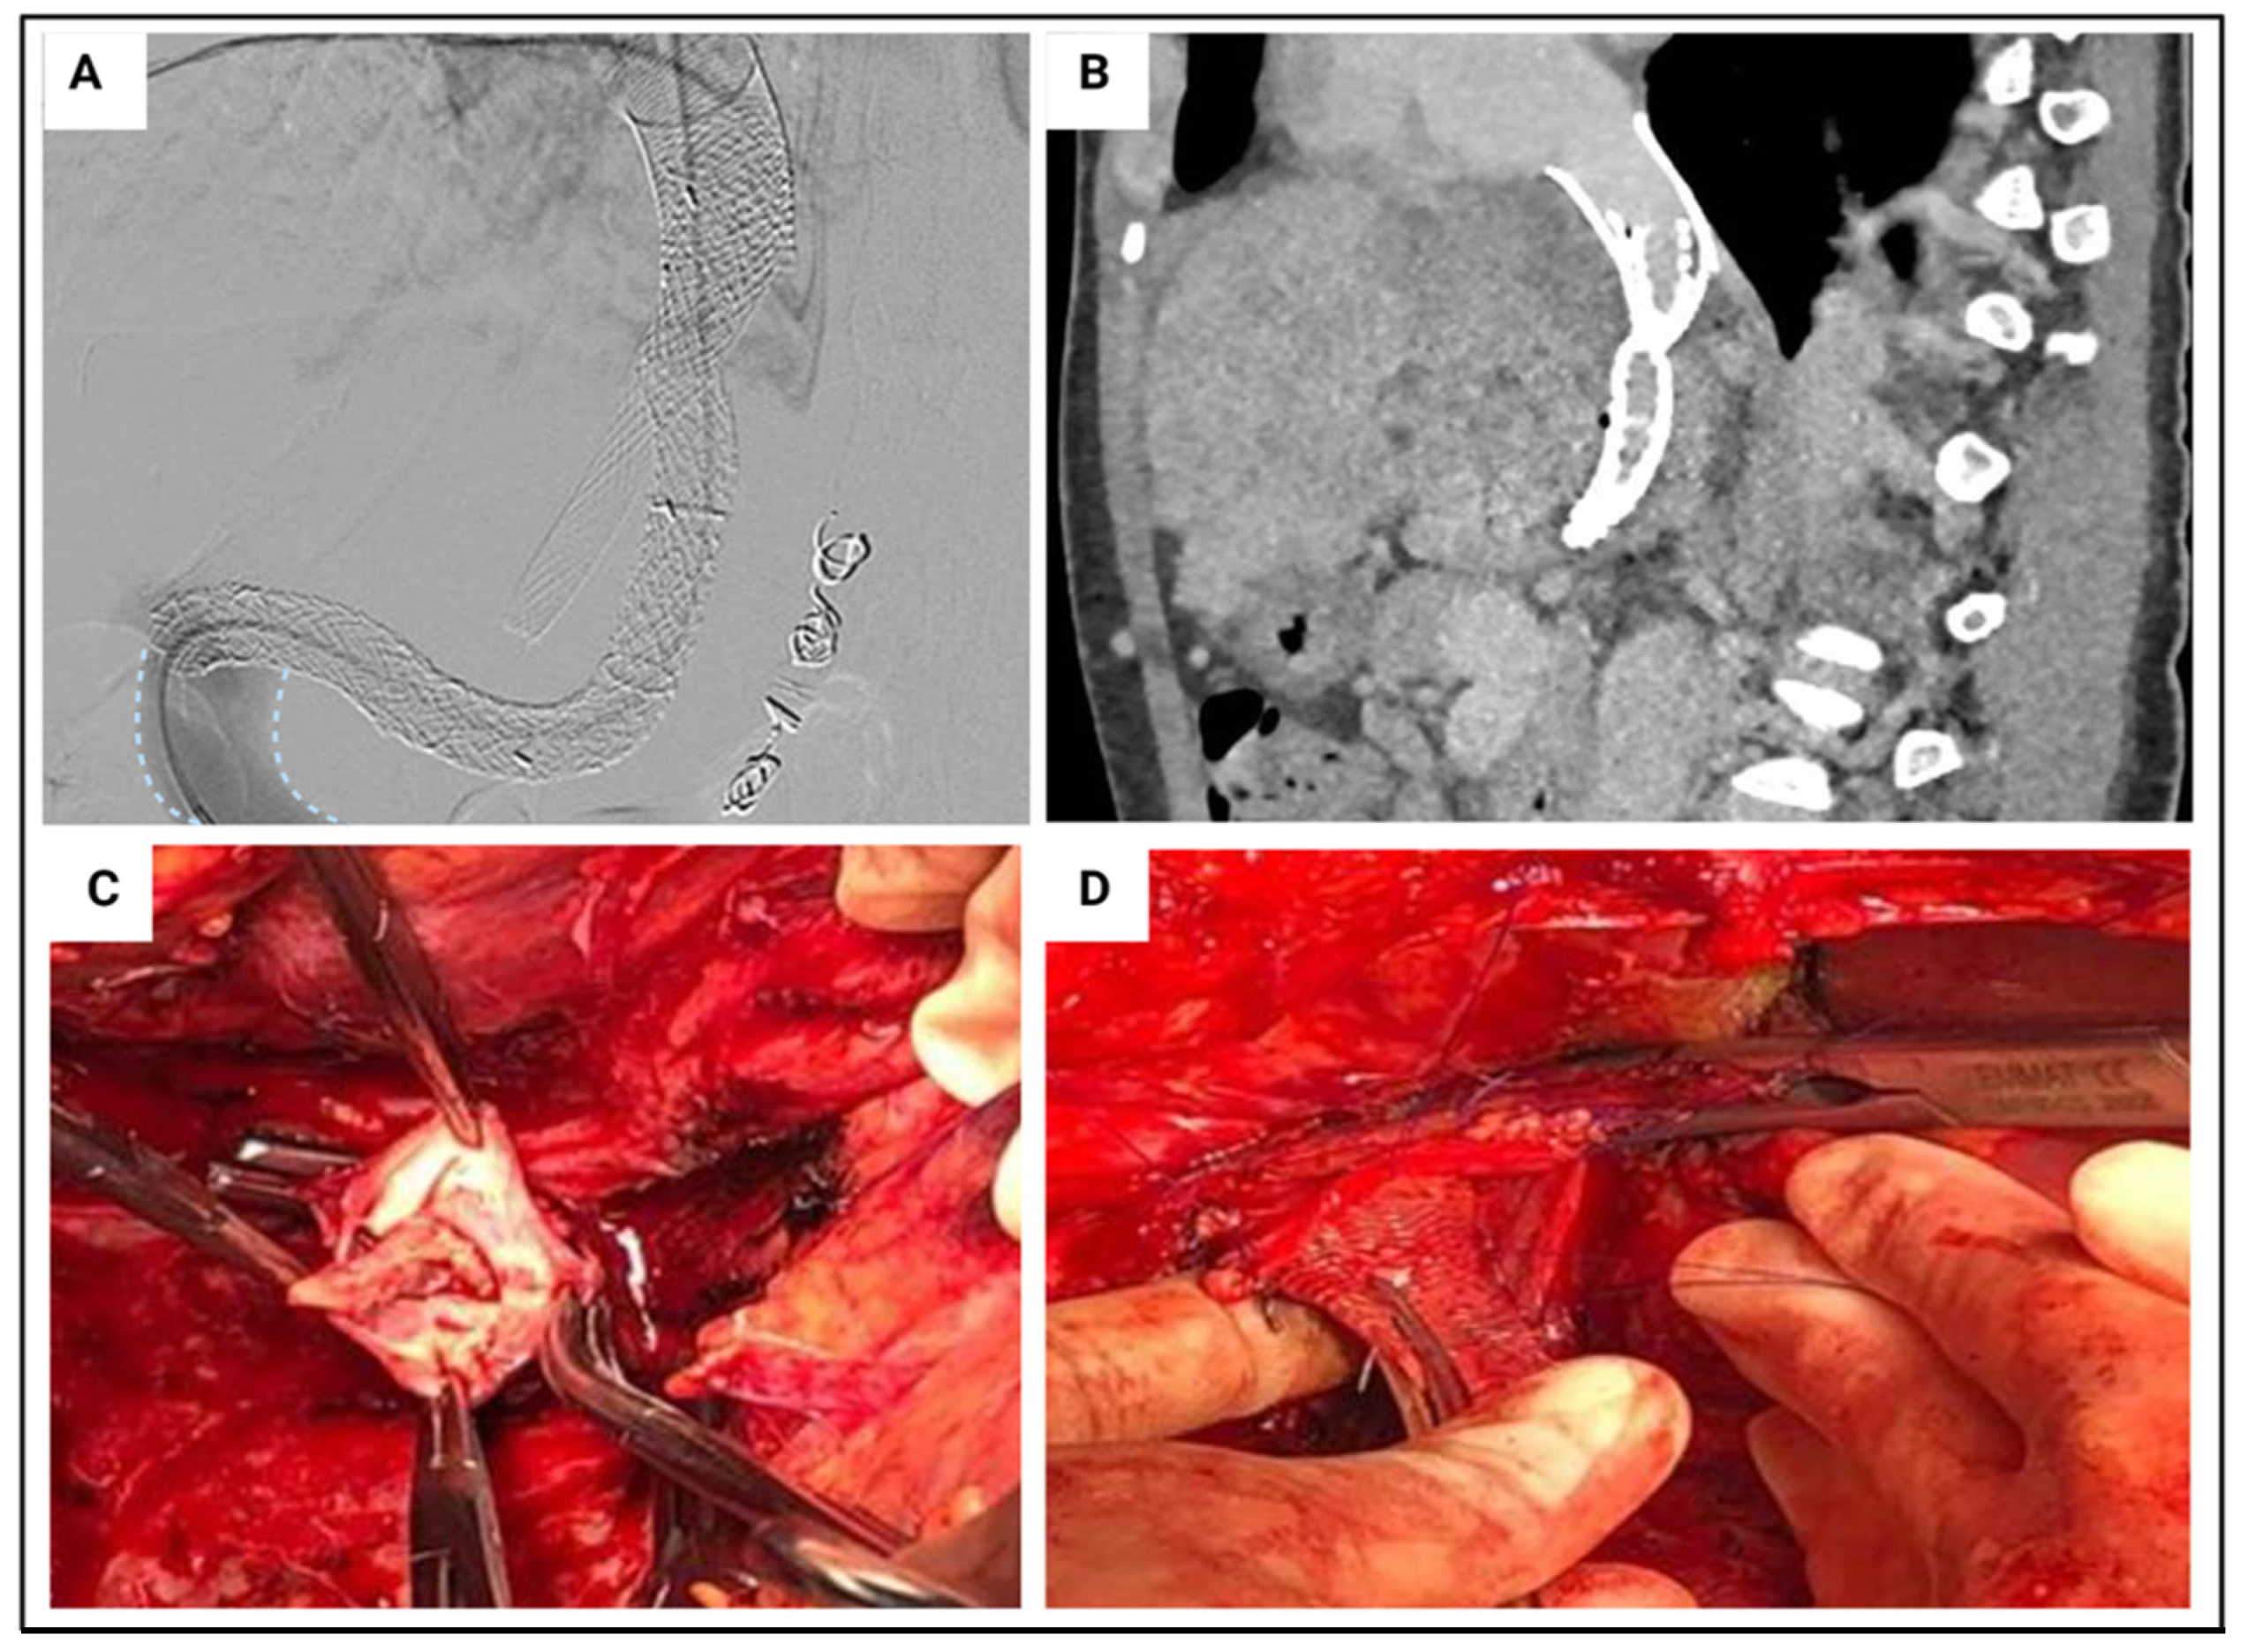

5.1. Retransplant

5.2. Previous Major Hepatobiliary Surgery

- Nasralla, D.; Lembach, H.; Mergental, H.; Mirza, D.; Friend, P.; Muiesan, P.; Perera, M. Ex Situ Arterial Reconstruction during Normothermic Perfusion of the Liver. Transplant. Direct. 2020, 6, e596. [Google Scholar] [CrossRef]